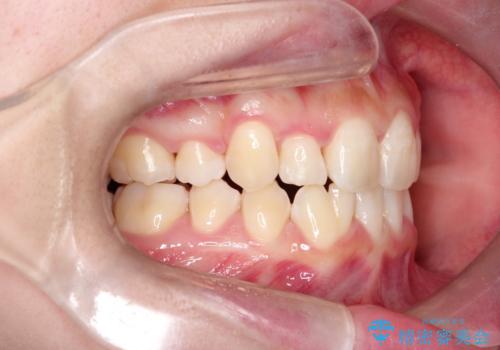

- 20代女性

- 1年9ヶ月

- 前歯のガタガタを主訴に来院されました。

抜歯を行い、インビザラインにて治療を完了しております。